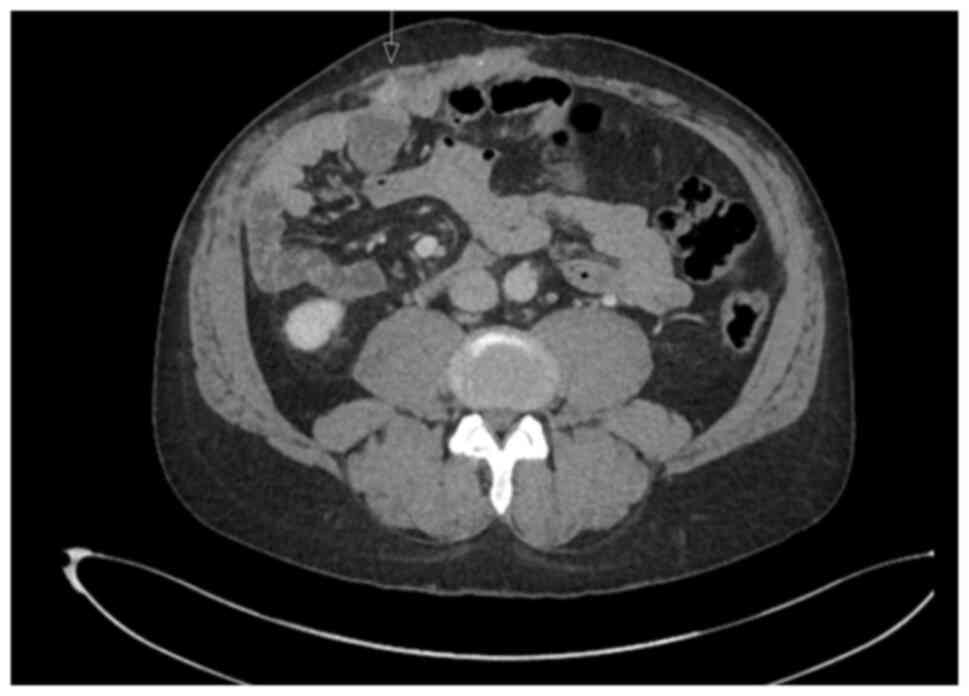

In July 2023, PET imaging revealed a new FDG-avid lesion in the anterior rectus sheath. Diagnostic biopsy was performed with histology again confirmed metastatic hCCA. The patient began systemic palliative chemotherapy. The patient began systemic palliative chemotherapy with gemcitabine (1,000 mg/m2 on days 1 and 8) and cisplatin (25 mg/m2 on days 1 and 8 of each 21-day cycle). By January, 2024, following eight cycles, surveillance imaging demonstrated increased uptake in a previously stable lung nodule. The rectus sheath metastasis and lung lesion were treated with surgical excision and microwave ablation, respectively. A new solitary lung recurrence was treated with ablation in October, 2024 (Figs. 8 and 9).

Axial computed tomography

demonstrating an FDG-avid soft tissue lesion in the anterior rectus

sheath, consistent with metastatic cholangiocarcinoma (white

arrow).

Figure 9

Axial computed tomography demonstrating an FDG-avid soft tissue lesion in the anterior rectus sheath, consistent with metastatic cholangiocarcinoma (white arrow).